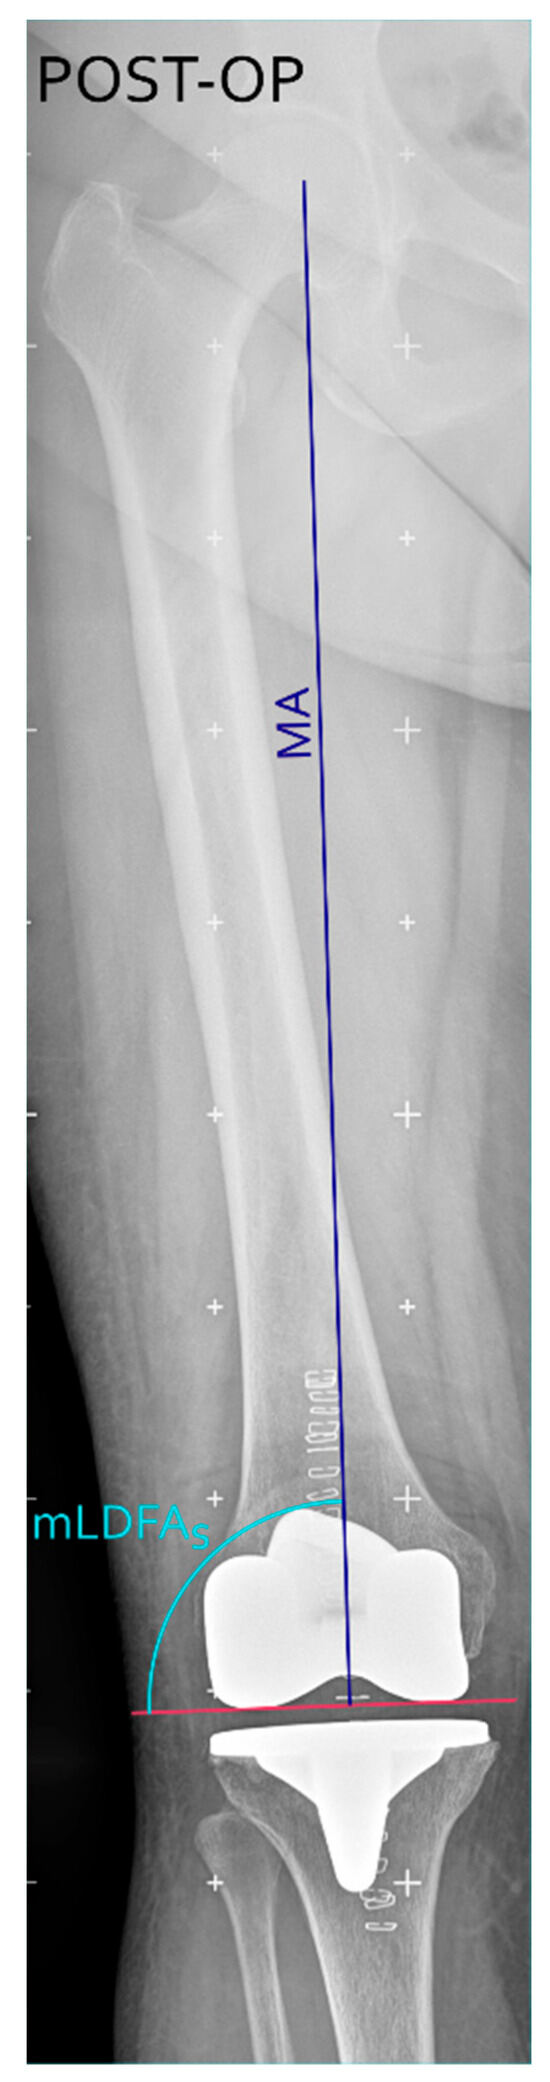

Background/Objectives: This study introduces and evaluates a novel surgical technique for total knee arthroplasty (TKA) that uses the trochlear groove bisector (TGB) as an anatomical landmark to achieve kinematic alignment of the femoral component in the coronal plane. The aim of the [...] Read more.

Background/Objectives: This study introduces and evaluates a novel surgical technique for total knee arthroplasty (TKA) that uses the trochlear groove bisector (TGB) as an anatomical landmark to achieve kinematic alignment of the femoral component in the coronal plane. The aim of the present retrospective observational analysis was to assess the reproducibility and accuracy of this approach and to report preliminary clinical outcomes. Methods: Twenty-eight TKA procedures were performed using the TGB-guided alignment technique. Preoperative planning and postoperative assessments were conducted on long-leg weight-bearing radiographs to measure the agreement between planned and achieved alignment, analysed using Bland–Altman statistics. Functional outcomes were evaluated at 12 months with the Knee Society Score (KSS), Forgotten Joint Score (FJS), and patient satisfaction. Results: The mean difference between planned and post-operative mLDFA was −0.3° ± 0.65°, with a root mean square error (RMSE) of 0.7°, demonstrating high accuracy and reproducibility. Postoperative outcomes showed mean KSS (knee = 89.6, function = 91.4), FJS = 69.6 ± 12, mean flexion = 124.6°, and mean HKA = 178°. Ninety percent of patients reported being satisfied or very satisfied at 12 months. Conclusions: The TGB-based technique offers a reliable, easily applicable method for restoring native femoral alignment in TKA using standard instrumentation. It allows accurate prediction of postoperative alignment and achieves favourable early functional outcomes. While currently limited to moderate varus deformities, future developments integrating 3D or CT-based planning may extend its applicability to more complex cases. Full article